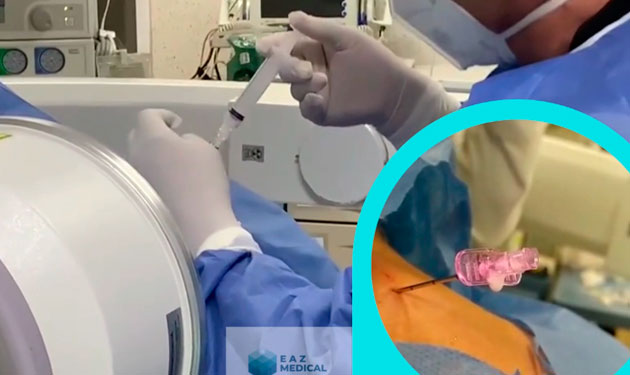

Radiofrecuencia en tratamiento de hernias discales.

Radiofrecuencia para tratar Radiculopatía lumbar.

Bloqueo del nervio occipital mayor

Radiofrecuencia en tratamiento de Neuralgía del Trigémino

Tratamiento de hernias cervicales

Bloqueo de Nervios Geniculados